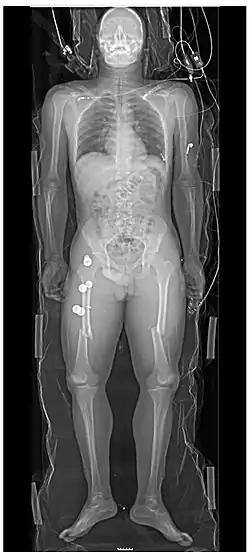

Traumatologie nebo též úrazová chirurgie je lékařský obor, který se zabývá akutním poraněním jakéhokoli orgánu v těle, nejenom kostí a pohybového aparátu. Traumatologie úzce souvisí s ortopedií, ale na rozdíl od ní se specializuje především na náhlá, často život ohrožující poranění. V nemocnicích vznikají oddělení traumatologie nebo urgentní příjmy nebo emergency. Pacient s poraněním je převezen sem a zde je vyhodnocen jeho stav, jsou zajištěny životní funkce a jednotlivá zranění řeší specialista z jiných oborů. Oddělení traumatologie mívají nepřetržitý provoz a zabývají se primárním ošetřením polytraumat, mnohočetných poranění a těžkých monotraumat.

- Chirurgická léčba – osteosyntéza (fixace kostí pomocí šroubů, destiček), artroskopie, náhrady kloubů.